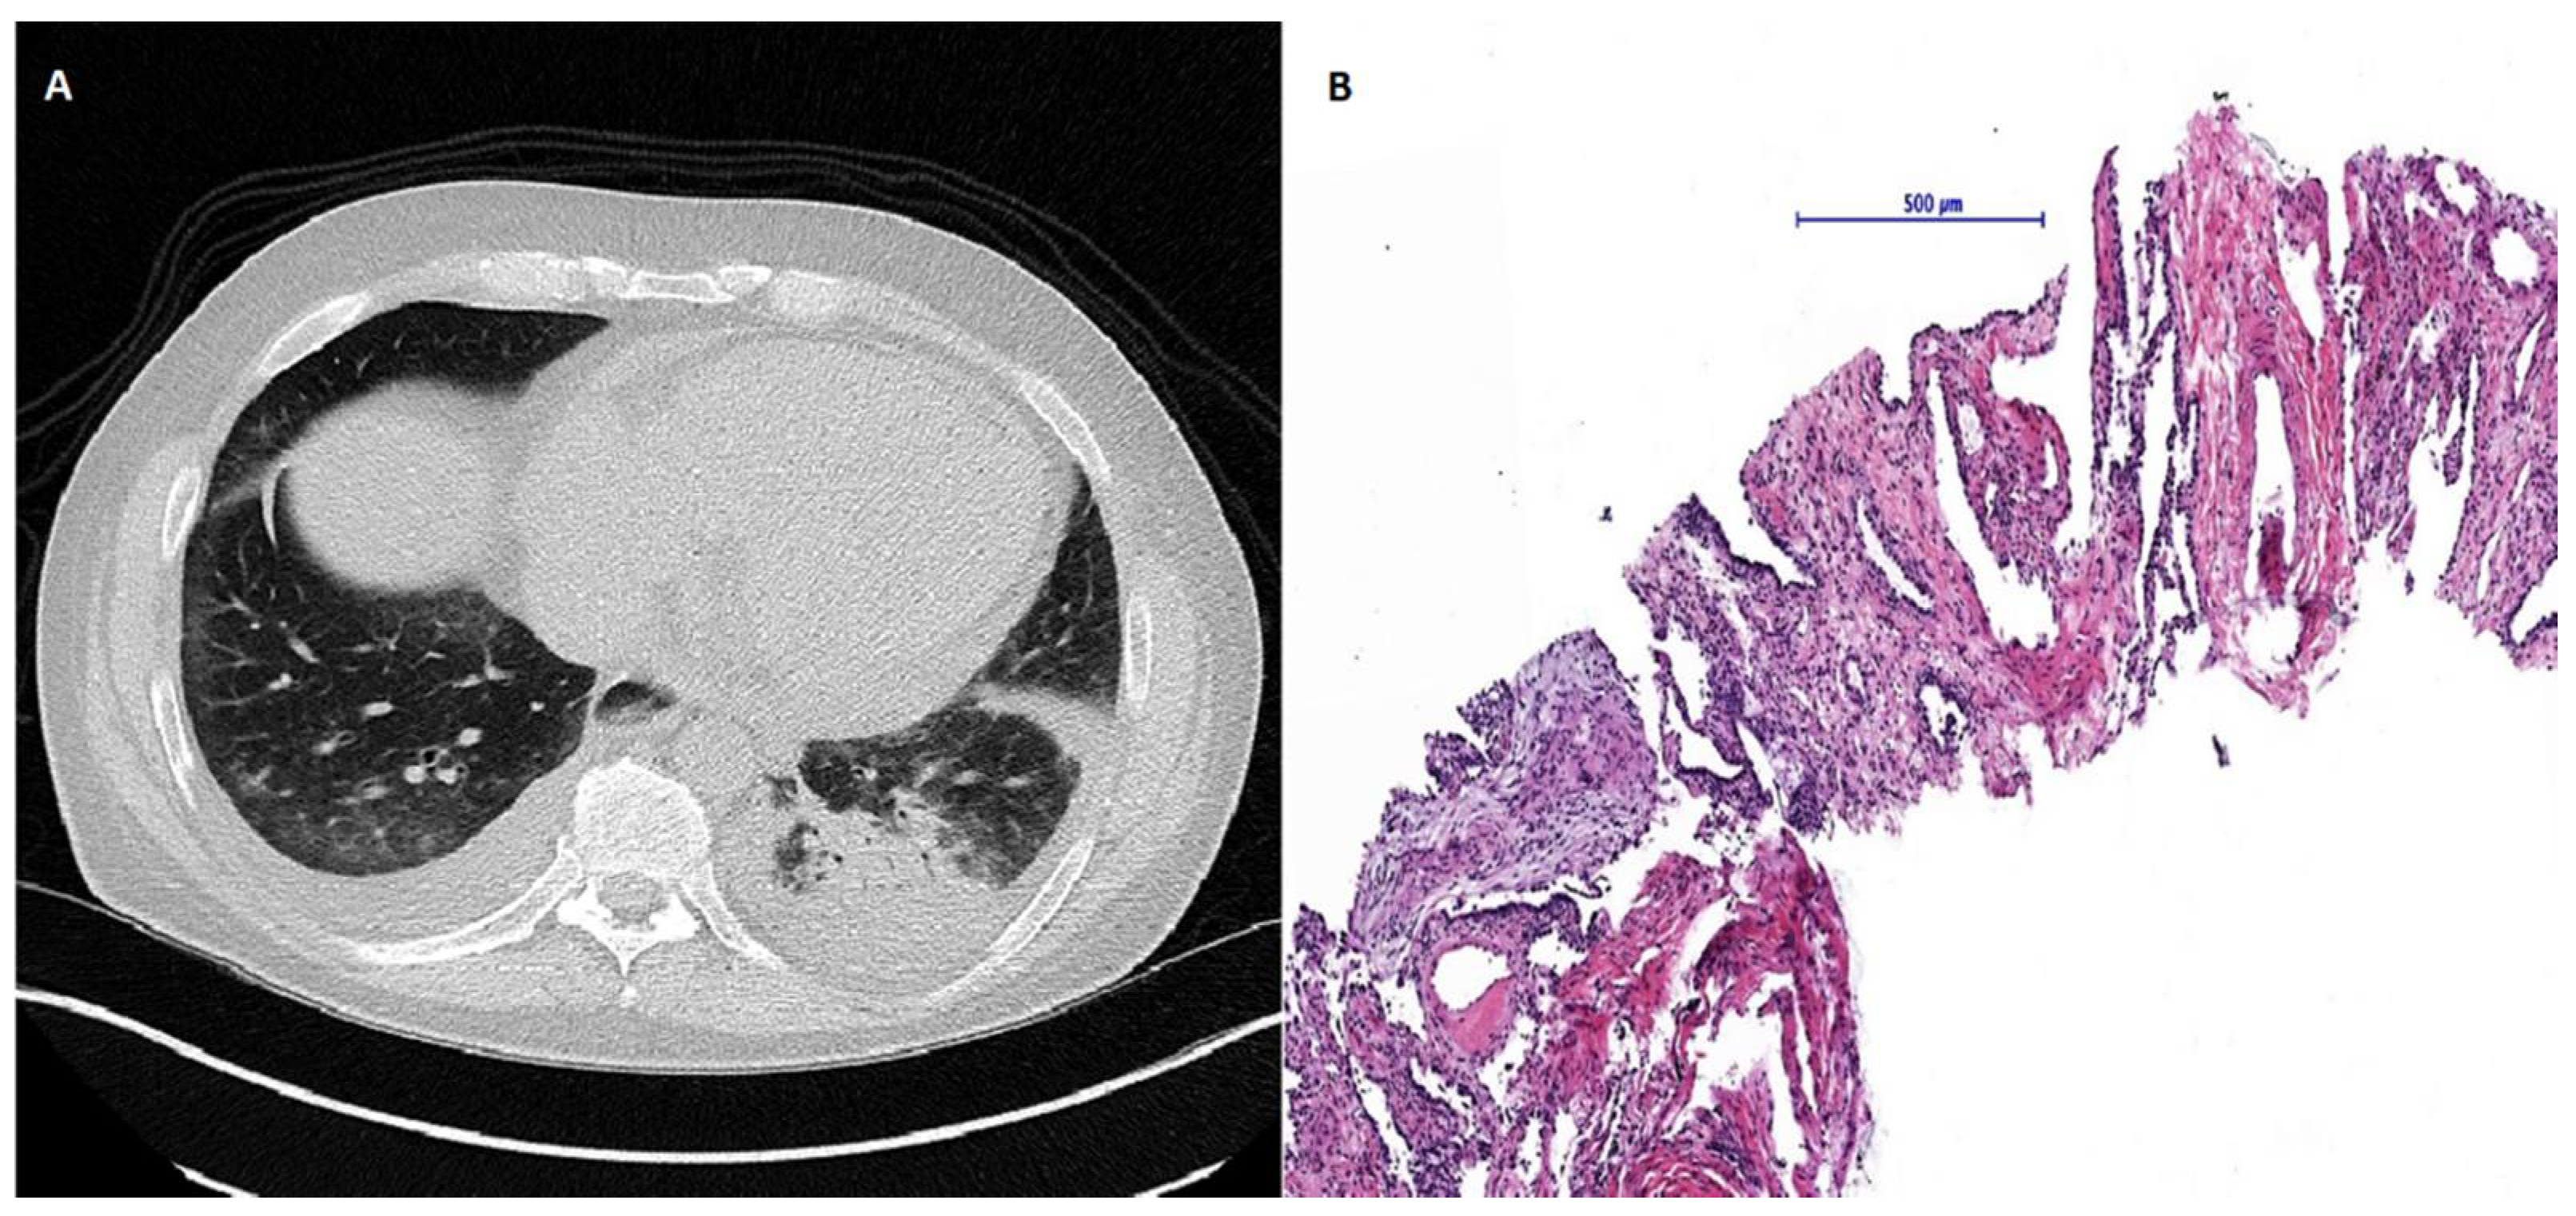

Due to active organ involvement, immunosuppressive therapy with rituximab (RTX) and mycophenolate mofetil (MMF) according to the Graz protocol [6] (Rituximab 500 mg: two intravenous infusions separated by 2 weeks every 3 months) was initiated as standard treatment with cyclophosphamide was refused by the patient. After immunosuppressive therapy and subsequent rehabilitation in May 2017, the patient’s initial symptoms improved with stable spirometry parameters and an ejection fraction of 55%; however, radiographic signs of the SSc-ILD did not improve and mRSS remained constantly at 11 points (Figure 1). Shortly after completion of the therapy, puffy fingers, acral necrosis of fingers and toes, and arthralgia of the ankles re-occurred and treatment with sildenafil was initiated. At the same time, spirometry parameters and echocardiographic findings (LVEF 50%) remained stable. In a follow-up visit in February 2018, NT-proBNP levels had increased significantly (18,287 pg/mL) accompanied by an increase of patient’s mRSS (14 points) (Figure 1) and persistent acral necrosis. Due to highly active multiple organ involvement and a high risk of disease progression, AHSCT was chosen as the next therapeutic option. In November 2018, the patient received AHSCT with a total of 2.08 × 106 CD34 + cells per kilogram of bodyweight positively selected stem cells. Conditioning regimen consisted of 148 mg/kg (= 8.8 g total dose) cyclophosphamide and 7.5 mg/kg of rabbit anti-lymphocyte globulin, and after continuous G-CSF stimulation from day five after AHSCT sustained neutrophil engraftment (absolute neutrophil count >0.5 G/L) was observed. Stem cell mobilization was performed with Granulocyte Colony-Stimulating Factor (10 microgram/kg bodyweight) for four days and at day 5 Plerixafor (0.24 mg/kg) was added due to insufficient CD 34 positive cell numbers in the peripheral blood. CD34+ enrichment and cryopreservation were done using the CliniMACS system (Miltenyi Biotec B.V. & Co. KG, 51429 Bergisch Gladbach, Germany) separating CD34 positive stem cells by magnetic beads from residual bone marrow cells. Eight days after AHSCT, the patient developed neutropenic fever and an increase of inflammatory parameters. HRCT of the lungs revealed ground glass opacities in both lower lobes with a consolidation in the left lower lobe (Figure 2). Lung function and mRSS (15 points) deteriorated (FVC 44.5% predicted, FEV1 35.1% predicted, FEV1/FVC ratio 72.75%, DLCO 40% predicted) (Figure 1). A consecutive bronchoscopy due to suspected pneumonia revealed no microbial growth in bronchoalveolar lavage. Despite intensified antibiotic and antifungal treatment, symptoms and radiographic findings did not improve. Subsequent percutaneous CT-guided lung biopsy revealed epithelioid cell pneumonia without a detectable pathogen (Figure 2).

Figure 2. (A) High-resolution computed tomography of the lungs revealed ground glass opacities in both lower lobes with a consolidation in the left lower lobe. (B) Histological presentation of changed lung parenchyma. Needle biopsy sample of lung parenchyma showed broad interalveolar septae with fibrous tissue and chronic inflammatory cells as well as reactive changed type 2 pneumocytes. Lower left part of the sample demonstrates merging epithelioid cell granulomas without necrosis within myofibroblastic proliferation.